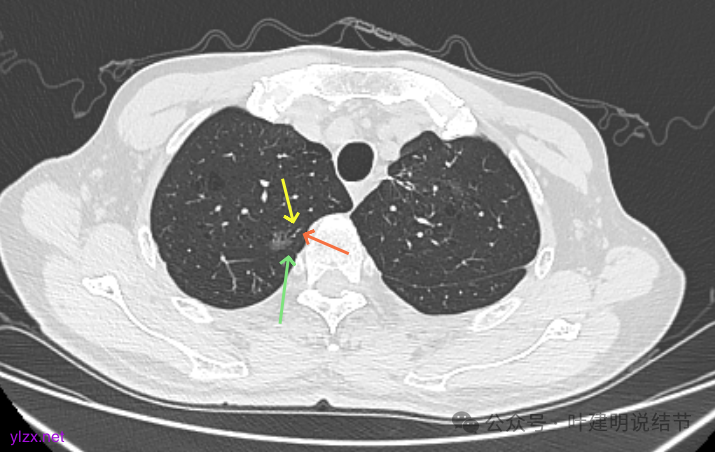

最后看2025年3月的连续层面的影像细节:

右上病灶淡磨密度,有空泡征,整体轮廓较清。

瘤肺边界清楚,空泡征明显。

表面不平,没有实性成分。灶内空泡有些像蜂窝状。

病灶边上有小血管走行,整体轮廓清,没有明显实性成分。

右上病灶淡而纯主要原因,空泡征明显。

左上病灶淡而纯,有微小血管进入。

右上淡磨,轮廓清,空泡明显。

左上的小而局部有细支气管扩张的样子,部分边缘显毛糙,有细毛刺样征。

右上叶病灶有血管贴边,轮廓清;

左上病灶纯磨,轮廓清。

右上淡磨,左下密度较右侧的稍不均一点。